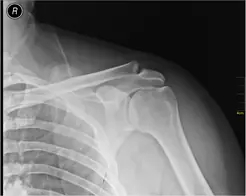

Luxations gleno-humerales